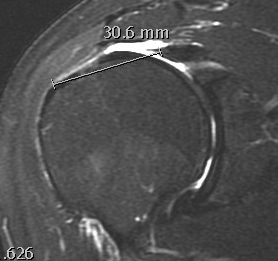

Measure tear in the coronal and sagittal plane

Small full thickness rotator cuff tear of supraspinatus - retracted to footprint

Large full thickness tear of supraspinatus and infraspinatus tendon - retracted to midhumeral head

Massive rotator cuff tear of the supraspinatus and infraspinatus tendon - retracted to glenoid